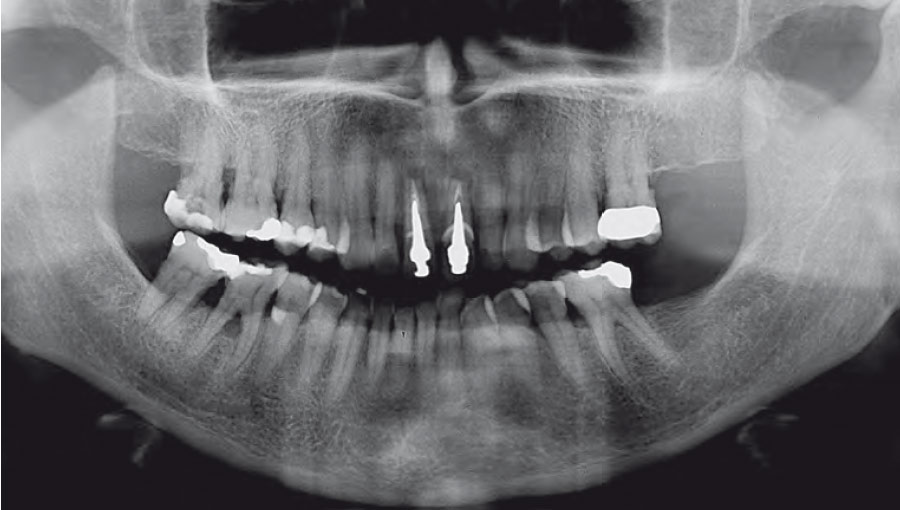

Si, infatti in ciascun capitolo sono presenti numerose immagini cliniche altamente esplicative

allo scopo di enfatizzare l'efficacia didattico-formativa del libro.

Nella gallery sotto alcune foto tratte dai capitoli del libro. Queste foto sono del prof. Eugenio Romeo